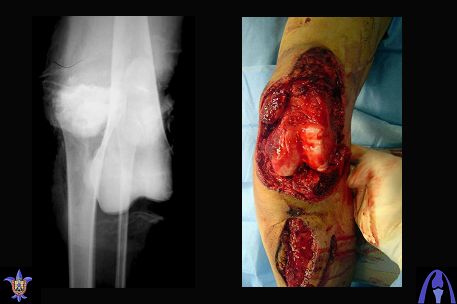

Bolnoi 27 let, DTP, Motorcycle trauma, postupil v kreane tiajelom sostoianii, osnovnia trauma- otkrity totalny vivih levogo kolennogo sustava s povrezdeniem malogo bersovogo nerva, tracionnoi povrezdenia podkolennoi arterii bez narushenia selostnost' sosuda, pomosh' okazanno v nujnum obmeme, kakoe ze mnenie uvazaemih kolleg naschet dalneshego vvedenia bolnogo? Castro

Uvajaemiy kollega! *Pomosh okazano v nujnom ob`eme*- kak ponyat? Vosstanovili krestoobraznih i bokovih svyazok? ili prosto vivih vpravili i fiksirovali AVF. sudya po R-snimkam nadkolennik nahoditsya visoko- znachit povrejdena i sobstvennaya svyazka, kotoraya ne ushita. Potom mojno sostavit plan lecheniya. S uvajeniem Abdurashid.

На ренгенограмме хорошая аппозиция костей коленного сустава, но надколенник находится подозрительно высоко, поэтому необходимо убедиться в отсутствии повреждения связки надколенника.